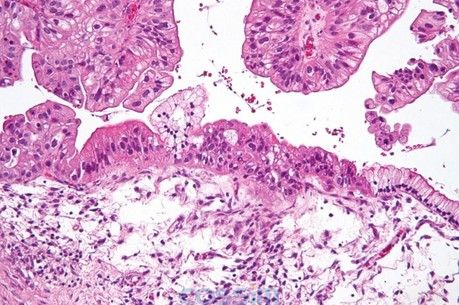

圖解:卵巢癌組織切片:圖為H&E染色后顯微鏡下的低度惡性潛能黏液性卵巢癌組織切片。圖的右方是正常的簡單黏液性上皮細胞,而圖的左方呈偽復(fù)層纖毛上皮處則被診斷為低度惡性潛能腫瘤細胞。

圖上方呈葉狀體結(jié)構(gòu)者為上皮細胞。